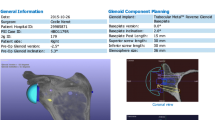

Seventeen patients, scheduled for a total shoulder arthroplasty (TSA) for primary glenohumeral osteoarthritis, were enrolled in this prospective, single centre study between April 2014 and October 2015. All the patients had a pre-operative CT scan of the entire shoulder (including medial border and inferior angle of the scapula), performed in the supine position, with the arm at side and with the shoulder in neutral rotation, with specific acquisition parameters (Fig. 1). The native DICOM axial views were used for pre-operative planning with Glenosys Software (Imascap, Plouzané, France). There were 14 women and three men, with mean age of 68 ± 12 years (range 48–87). All the subjects were provided clear information and gave written consent for a post-operative CT scan, before inclusion. This study received an Institutional Review Board agreement (Centre Orthopédique Santy, IRB 20.1611).

Pre-operative planning

Using specific validated algorithms, Glenosys Software performs automatic 3D reconstruction of the scapula and precisely determines glenoid version, inclination, and humeral head subluxation, with respect to the scapular plane [20, 21]. This software was used by the surgeons to analyze glenoid deformity and to virtually implant the glenoid component for each patient before surgery. All the pre-operative shoulder parameters (version, inclination, humeral head subluxation, and glenoid type according to Walch classification [22]) were recorded for analysis (Table 1). The surgeon had to choose component size and radius of curvature, as well as the optimal position with respect to orientation (< 10° superior inclination, < 15° retroversion), implant-on-bone seating (min. 80%), subchondral bone preservation, and avoiding glenoid vault perforation, based on previously published data [4,5,6,7,8,9]. The virtual component parameters (type, position, orientation) were created by 3D models saved in a Standard Tessellation Language (.STL) file format, as well as the 3D pre-operative scapula. These two .STL files (“pre-op scapula” and “pre-op implant”) were subsequently used for comparison with post-operative real position of the implant.